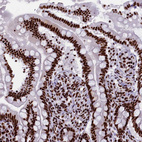

Immunohistochemical staining of human endometrium shows strong nuclear positivity in glandular cells.